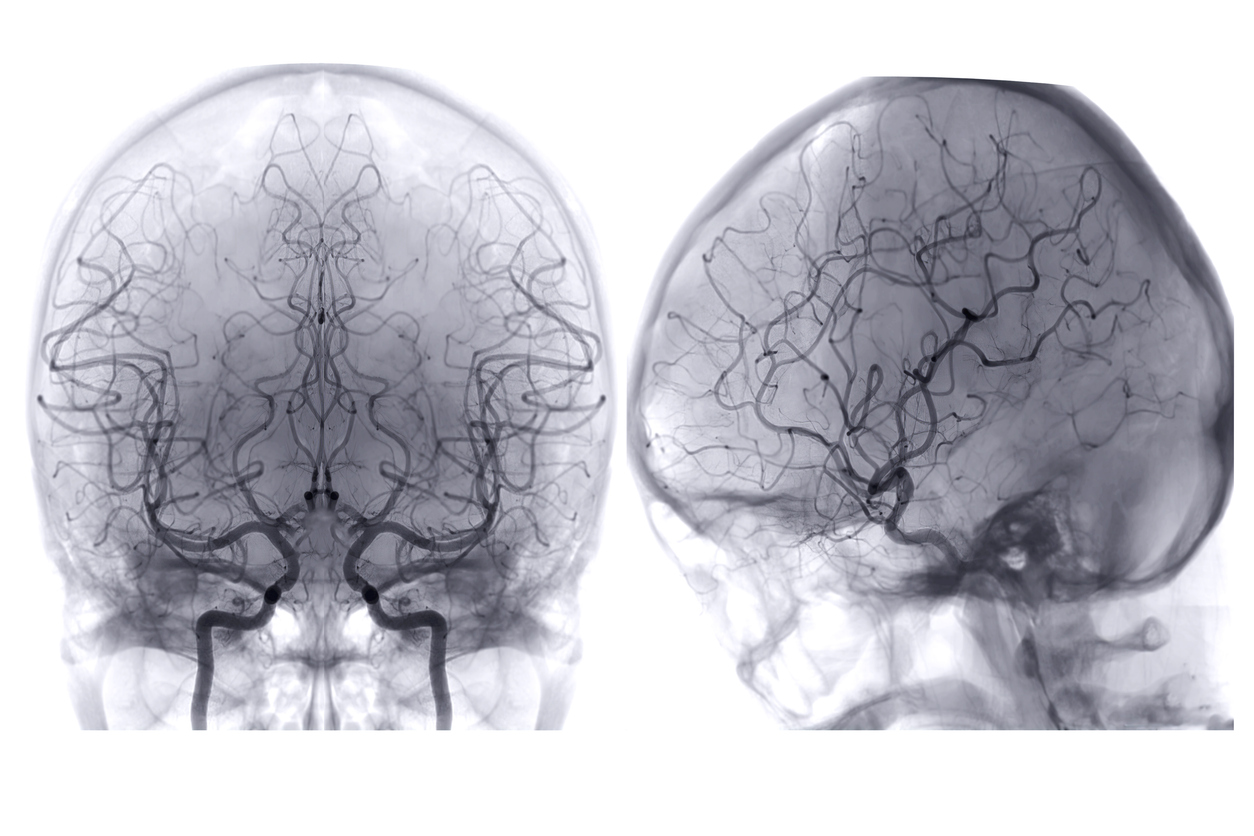

A Loss of Proper Brain Blood Flow

Blood carries essential components to the brain, like oxygen and sugar (glucose), providing energy to support brain activity. Brain blood flow decreases normally with age, and even more with Alzheimer’s. The decline seen in Alzheimer’s can significantly impact brain activity—making even the most basic cell functions difficult. This can have wide-ranging implications for cells and overall brain health and likely contributes to cognitive decline.

Alzheimer’s Disease Research grantee Dr. Marta Casquero-Veiga is developing new imaging tools to identify small brain blood clots that develop in Alzheimer’s. Learn more.